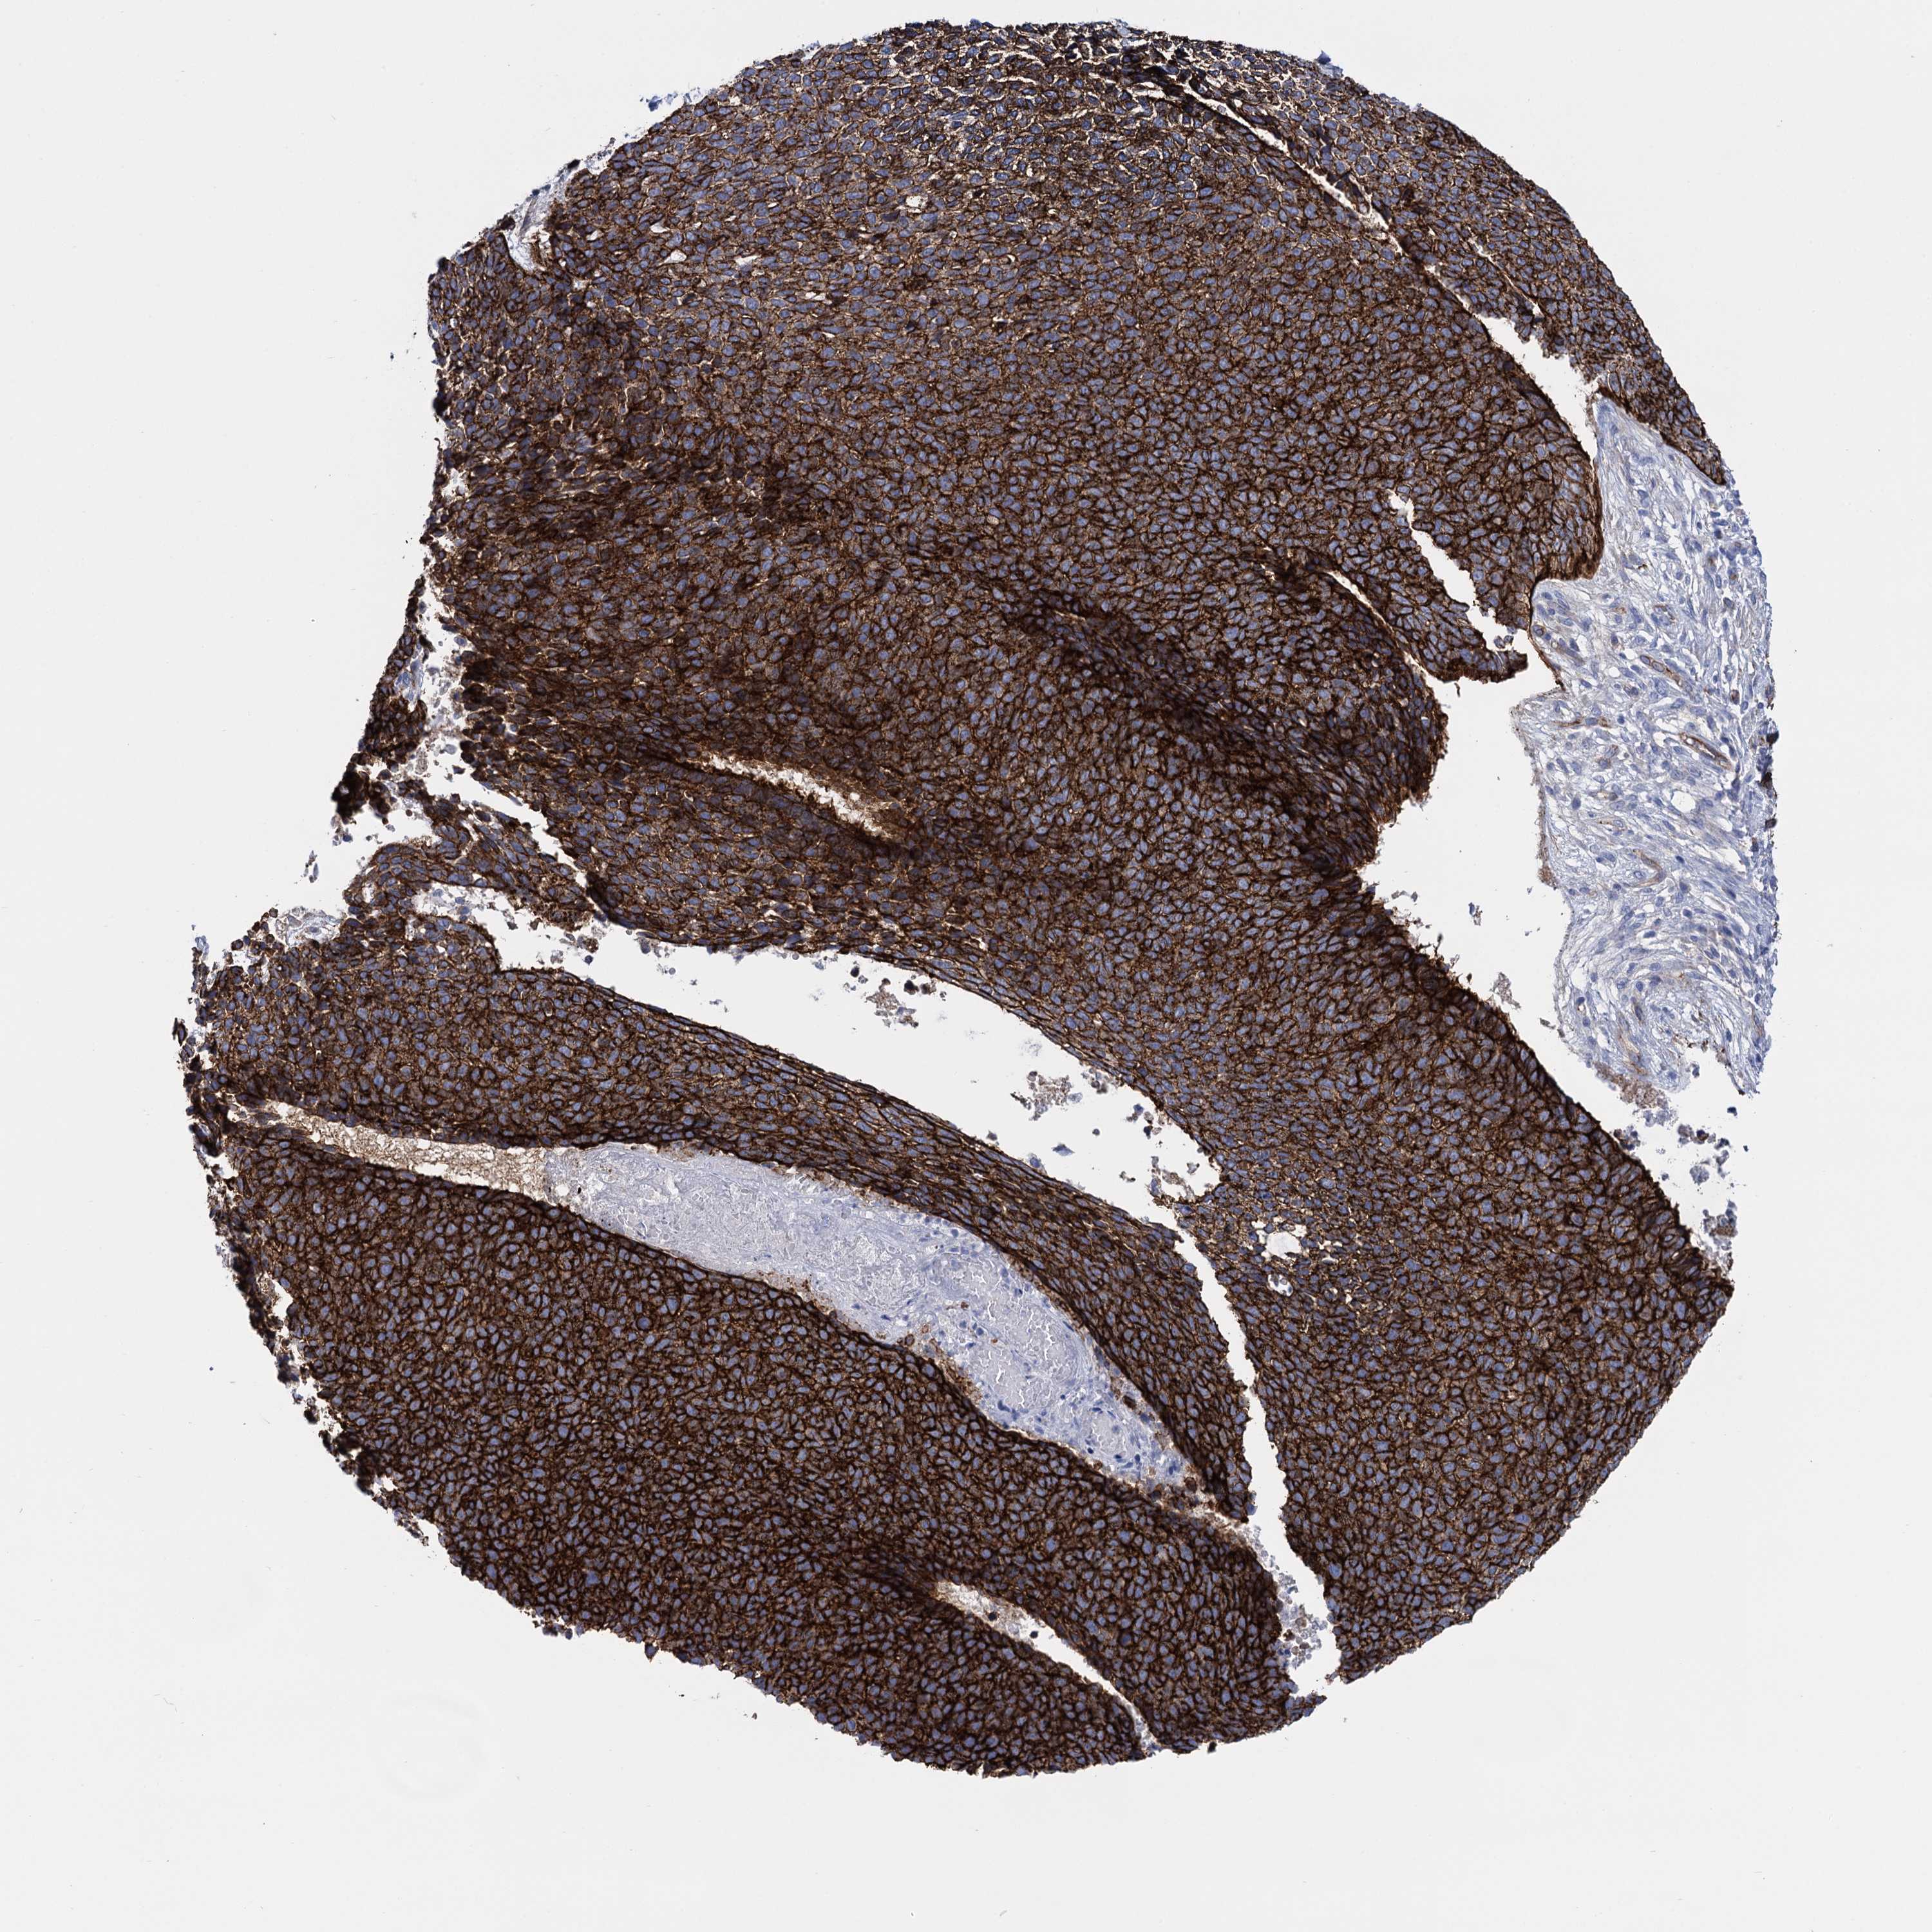

SKIN CANCER - Protein expressioni

A mouse-over function shows sample information and annotation data. Click on an image to view it in a full screen mode. Samples can be filtered based on level of antibody staining by selecting one or several of the following categories: high, medium, low and not detected. The assay and annotation is described here.

Antibody stainingi

Antibody staining in the annotated cell types in the current human tissue is reported as not detected, low, medium, or high, based on conventional immunohistochemistry profiling in selected tissues. This score is based on the combination of the staining intensity and fraction of stained cells.

Each image is clickable and will lead to virtual microscopy that enables deeper exploration of all samples and also displays staining intensity scores, fraction scores and subcellular localization as well as patient and tissue information for each sample.

Antibody HPA014404

Antibody CAB001452

Antibody CAB040581

Antibody CAB080022

Staining

High

Medium

Low

Not detected

Intensity

Strong

Moderate

Weak

Negative

Quantity

>75%

75%-25%

<25%

None

Location

Nuclear

Cytoplasmic/membranous

Cytoplasmic/membranous,nuclear

Squamous cell carcinoma, NOS

Basal cell carcinoma

Adnexal tumor, benign

Squamous cell carcinoma, metastatic, NOS